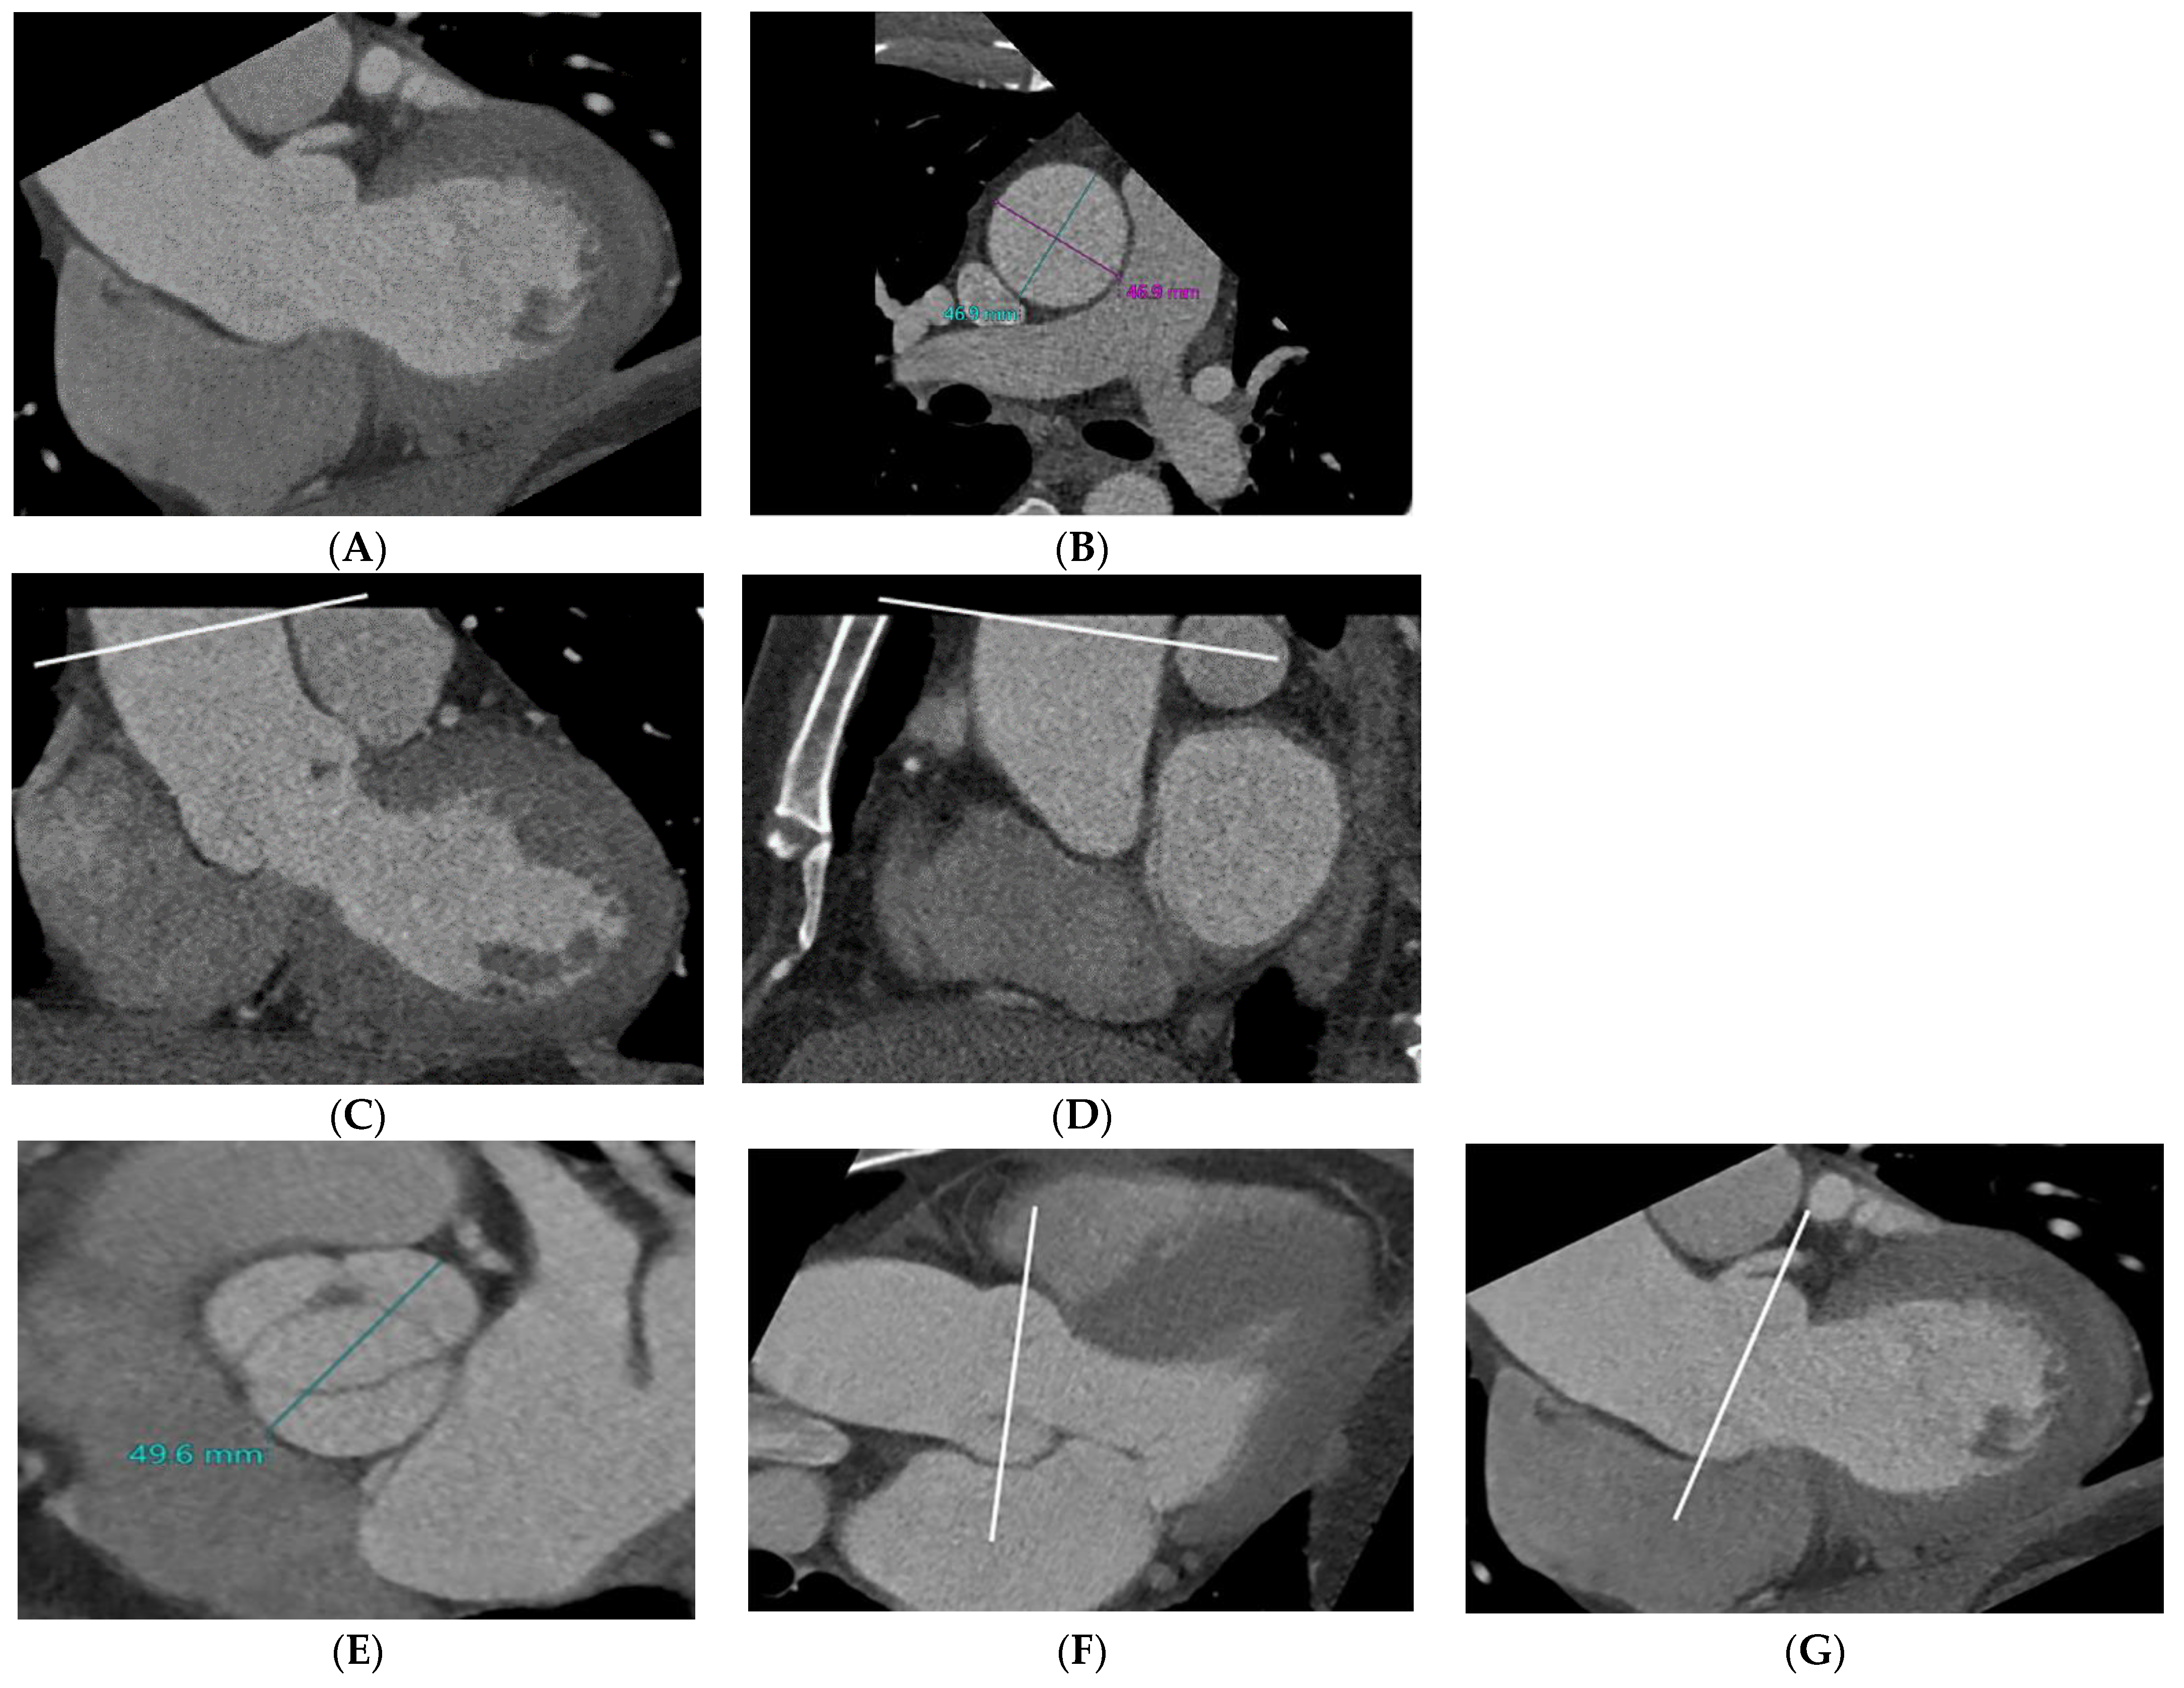

2.2. CT Imaging Protocols

2.3. CT Image Reconstruction and Analysis